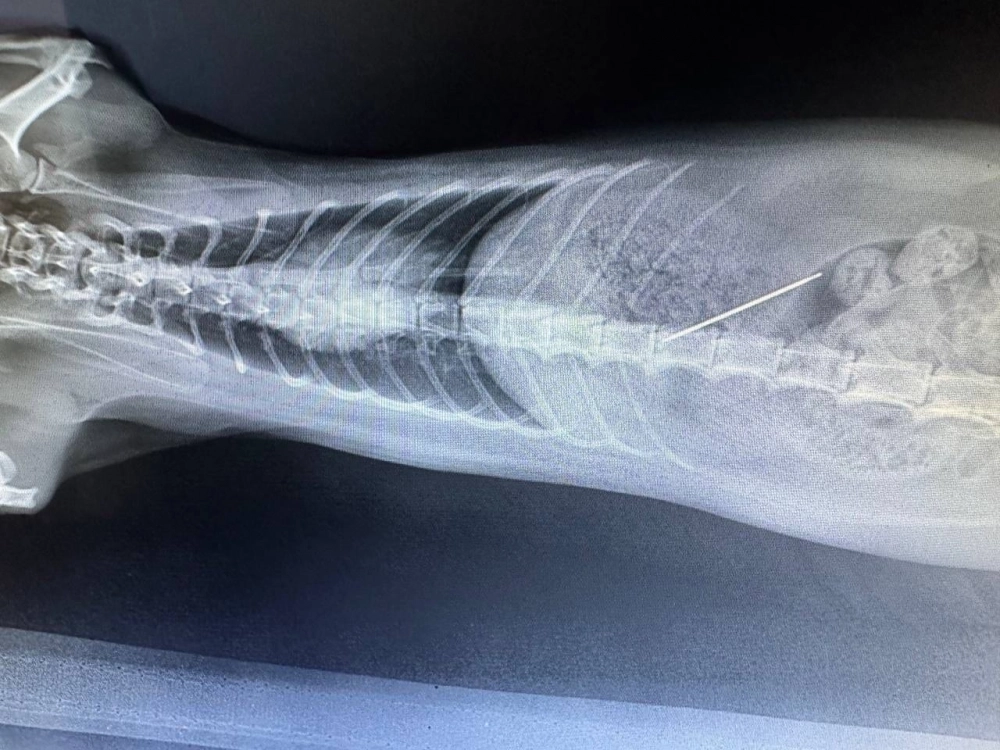

Хозяева срочно обратились в клинику. Рентген подтвердил, что игла находится в желудке животного – требовалось немедленное вмешательство.

Ветеринар Александра Полиновская успешно провела операцию и извлекла инородный предмет. Кошке назначили курс антибиотиков для профилактики осложнений и восстановления.